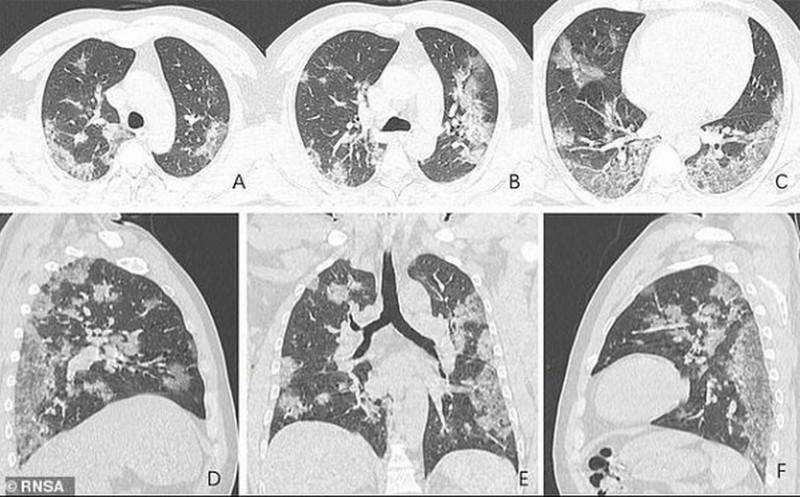

КТ

Компьютерная томография (КТ) создает подробные качественные изображения костей, кровеносных сосудов (при внутривенном контрастировании во время исследования), мягких тканей и органов. Исследование используют для диагностики онкологических заболеваний, травм, сосудистых патологий, поражения легких, брюшной полости и т.д.

КТ-аппарат выглядит как большой «бублик». Пациент лежит на столе, который постепенно движется, пока аппарат вращается вокруг и создает изображения поперечного сечения тела под разными углами. Затем изображения выводятся на экран компьютера, и с помощью цифровых алгоритмов создается трехмерное изображение.

Рентгеновские аппараты в некоторых случаях не могут диагностировать повреждения мышц, мягких тканей или других органов тела, что возможно с помощью компьютерной томографии. Кроме того, рентгеновские изображения представлены в 2D-формате, а изображения компьютерной томографии — в 3D.

COVID виден на томограмме даже не специалисту

Пресловутый COVID во многих случаях первично диагностируется уже на обычных рентгеновских снимках. То же с другими проблемами легких.

Даже на рентгеновских плоских снимках видно COVID